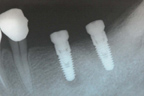

左下顎植入兩顆牙根。

X光片顯示植體位置。